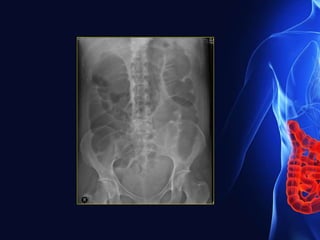

On Plain films

• Dilated gas & fluid filled loops of small bowel.

• Multiple fluid level

• Dilated fluid-filled loops of small bowel may be

identified as oval or round soft tissue densities that

changes with position.

• Absent or little air in large bowel